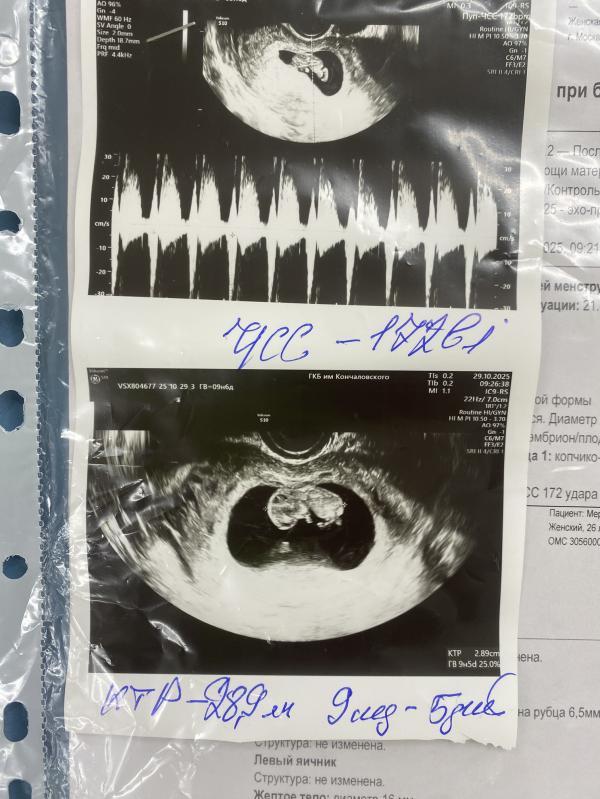

На девочку 143 чсс было 10 Нед

Чсс большая, возможно девочка😂

С дочкой было 160 вот сейчас посмотрела ) не знаю не знаю) пойду сдавать кровь на определение пола